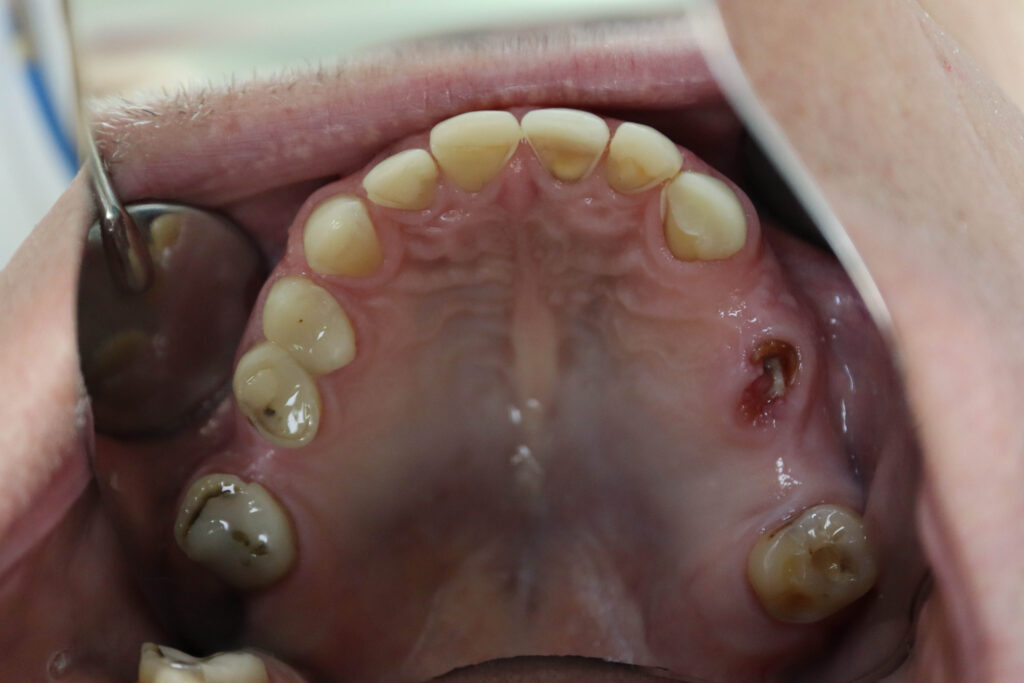

Ситуация до лечения

пациент до имплантации